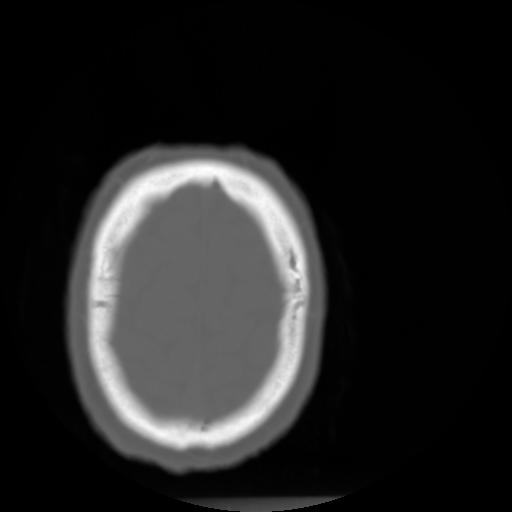

3 CEREBRO,,Axial,3.0,CEREBRO,,